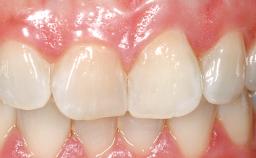

A 30-year-old female patient had lost tooth 21 and was referred to our clinic for consultation and treatment. Due to advanced apical infection, tooth 21 had been extracted two months earlier at another clinic and an acrylic-resin tooth had been bonded to the adjacent teeth. The patient desired implant treatment to avoid any damage to the adjacent natural teeth. While the patient had no history of any systemic disorder, she was a heavy smoker and exhibited medium to advanced periodontitis in the entire jaw. After the initial treatment to achieve a pocket probing depth of less than 4 mm and no bleeding on probing, a decrease in the height of the papillae mesial and distal to the extraction site and overall gingival recession were observed.

| Soft Tissue Contour and Volume | Slightly compromised |